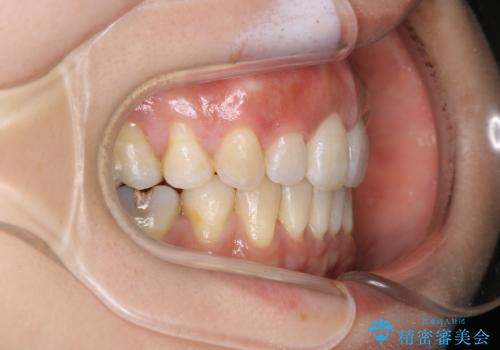

著しい八重歯が気になる インビザラインでの矯正治療